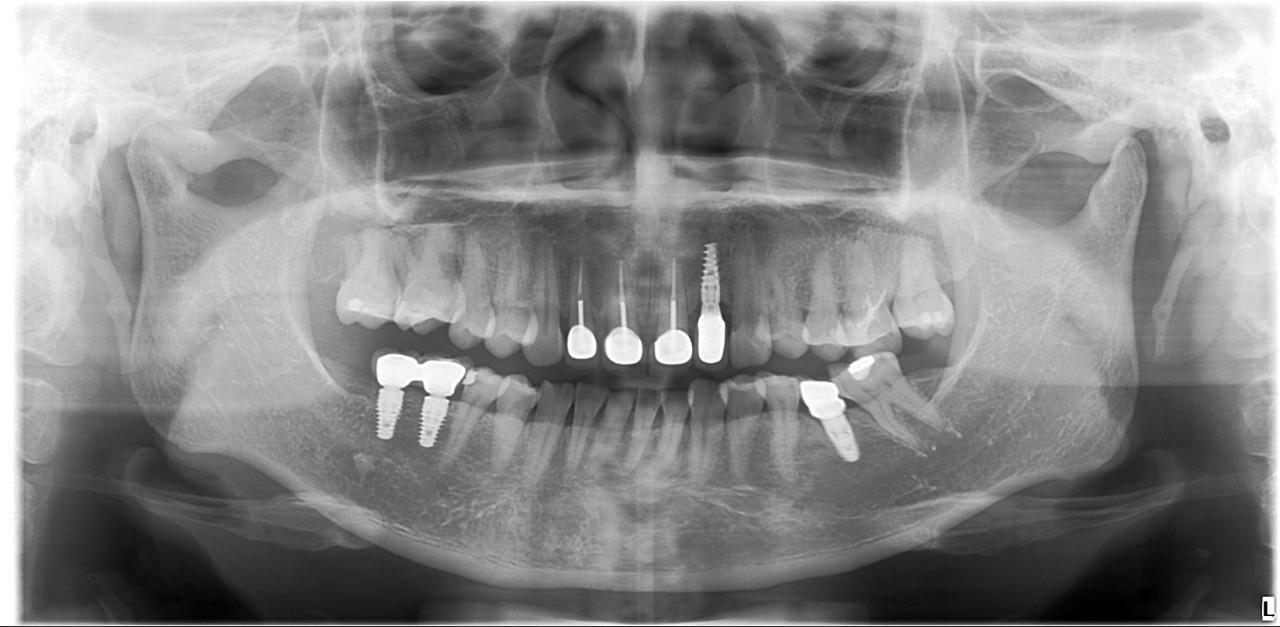

Cấy ghép răng (Implant) : Đây là phương pháp phổ biến và hiệu quả nhất để phục hồi răng đã mất. Cấy ghép răng giúp phục hồi chức năng nhai và ngăn ngừa tình trạng teo xương hàm. Cấy ghép được cấy vào xương hàm và có thể lắp răng giả lên đó.

Nếu bạn mất răng lâu ngày, hãy tham khảo ý kiến bác sĩ nha khoa để chọn phương pháp phục hồi phù hợp. Việc phục hồi răng càng sớm càng tốt sẽ giúp hạn chế các tác động tiêu cực đối với xương hàm và các răng còn lại.